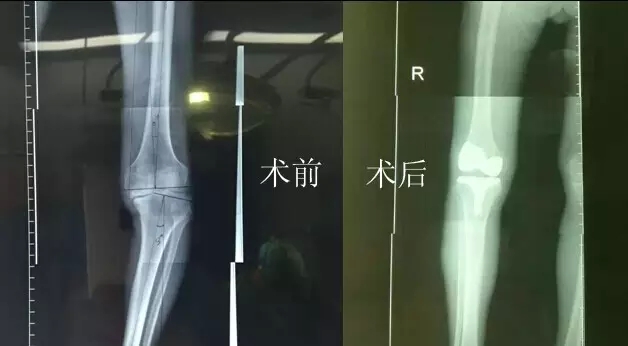

“嚴(yán)老伯的右膝患有重度關(guān)節(jié)骨性關(guān)節(jié)炎,右膝內(nèi)翻畸形,如果再晚點(diǎn)來就醫(yī),他的狀況還會持續(xù)變壞。”危立軍替嚴(yán)老伯仔細(xì)檢查之后說,“鑒于他的情況,我們建議實(shí)行人工膝關(guān)節(jié)表面置換術(shù)。”

今天上午,主治醫(yī)生危立軍巡查病房時說:“嚴(yán)老伯的手術(shù)很成功,病人是非常嚴(yán)重的屈曲攣縮并內(nèi)翻畸形,膝關(guān)節(jié)平臺內(nèi)側(cè)骨缺損很嚴(yán)重。但我們采取了目前國際上最先進(jìn)的手術(shù)方法,無痛化病房管理和快速康復(fù)理念,所以病人恢復(fù)很快。”

據(jù)了解,以前像做這樣的手術(shù),病人大概需要休息兩個月左右才能逐漸康復(fù),而采取新的手術(shù)方法,按照嚴(yán)老伯目前恢復(fù)的情況,不需要什么特殊康復(fù),一周左右就能下地行走,兩周后就能出院。嚴(yán)老伯和家人對這次手術(shù)也表示非常滿意,他的關(guān)節(jié)內(nèi)翻也恢復(fù)到正常人一樣。